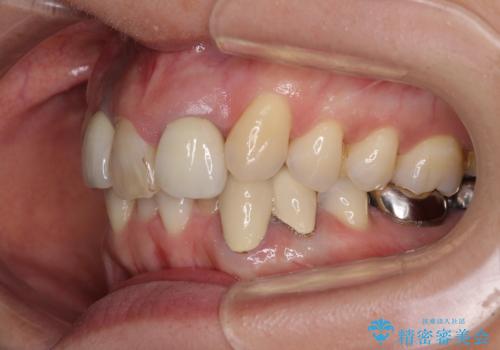

- 非対称な前歯や奥歯の目立つ銀歯を気にして来院された患者様です。

左上前から2番目の歯は、以前裏側に位置していたことから抜歯をされていましたが、前歯の非対称が長年気になっているとのことでした。

矯正治療によって前歯にスペースを作り、左右対称となるようにオールセラミッククラウンにて補綴治療を行うとしました。

他にも奥歯の咬み合わせに問題があったので、全顎的な矯正治療を行い、前歯以外にも口を開けたときに目立つ奥の銀歯をセラミッククラウンにて補綴治療を行うこととしました。